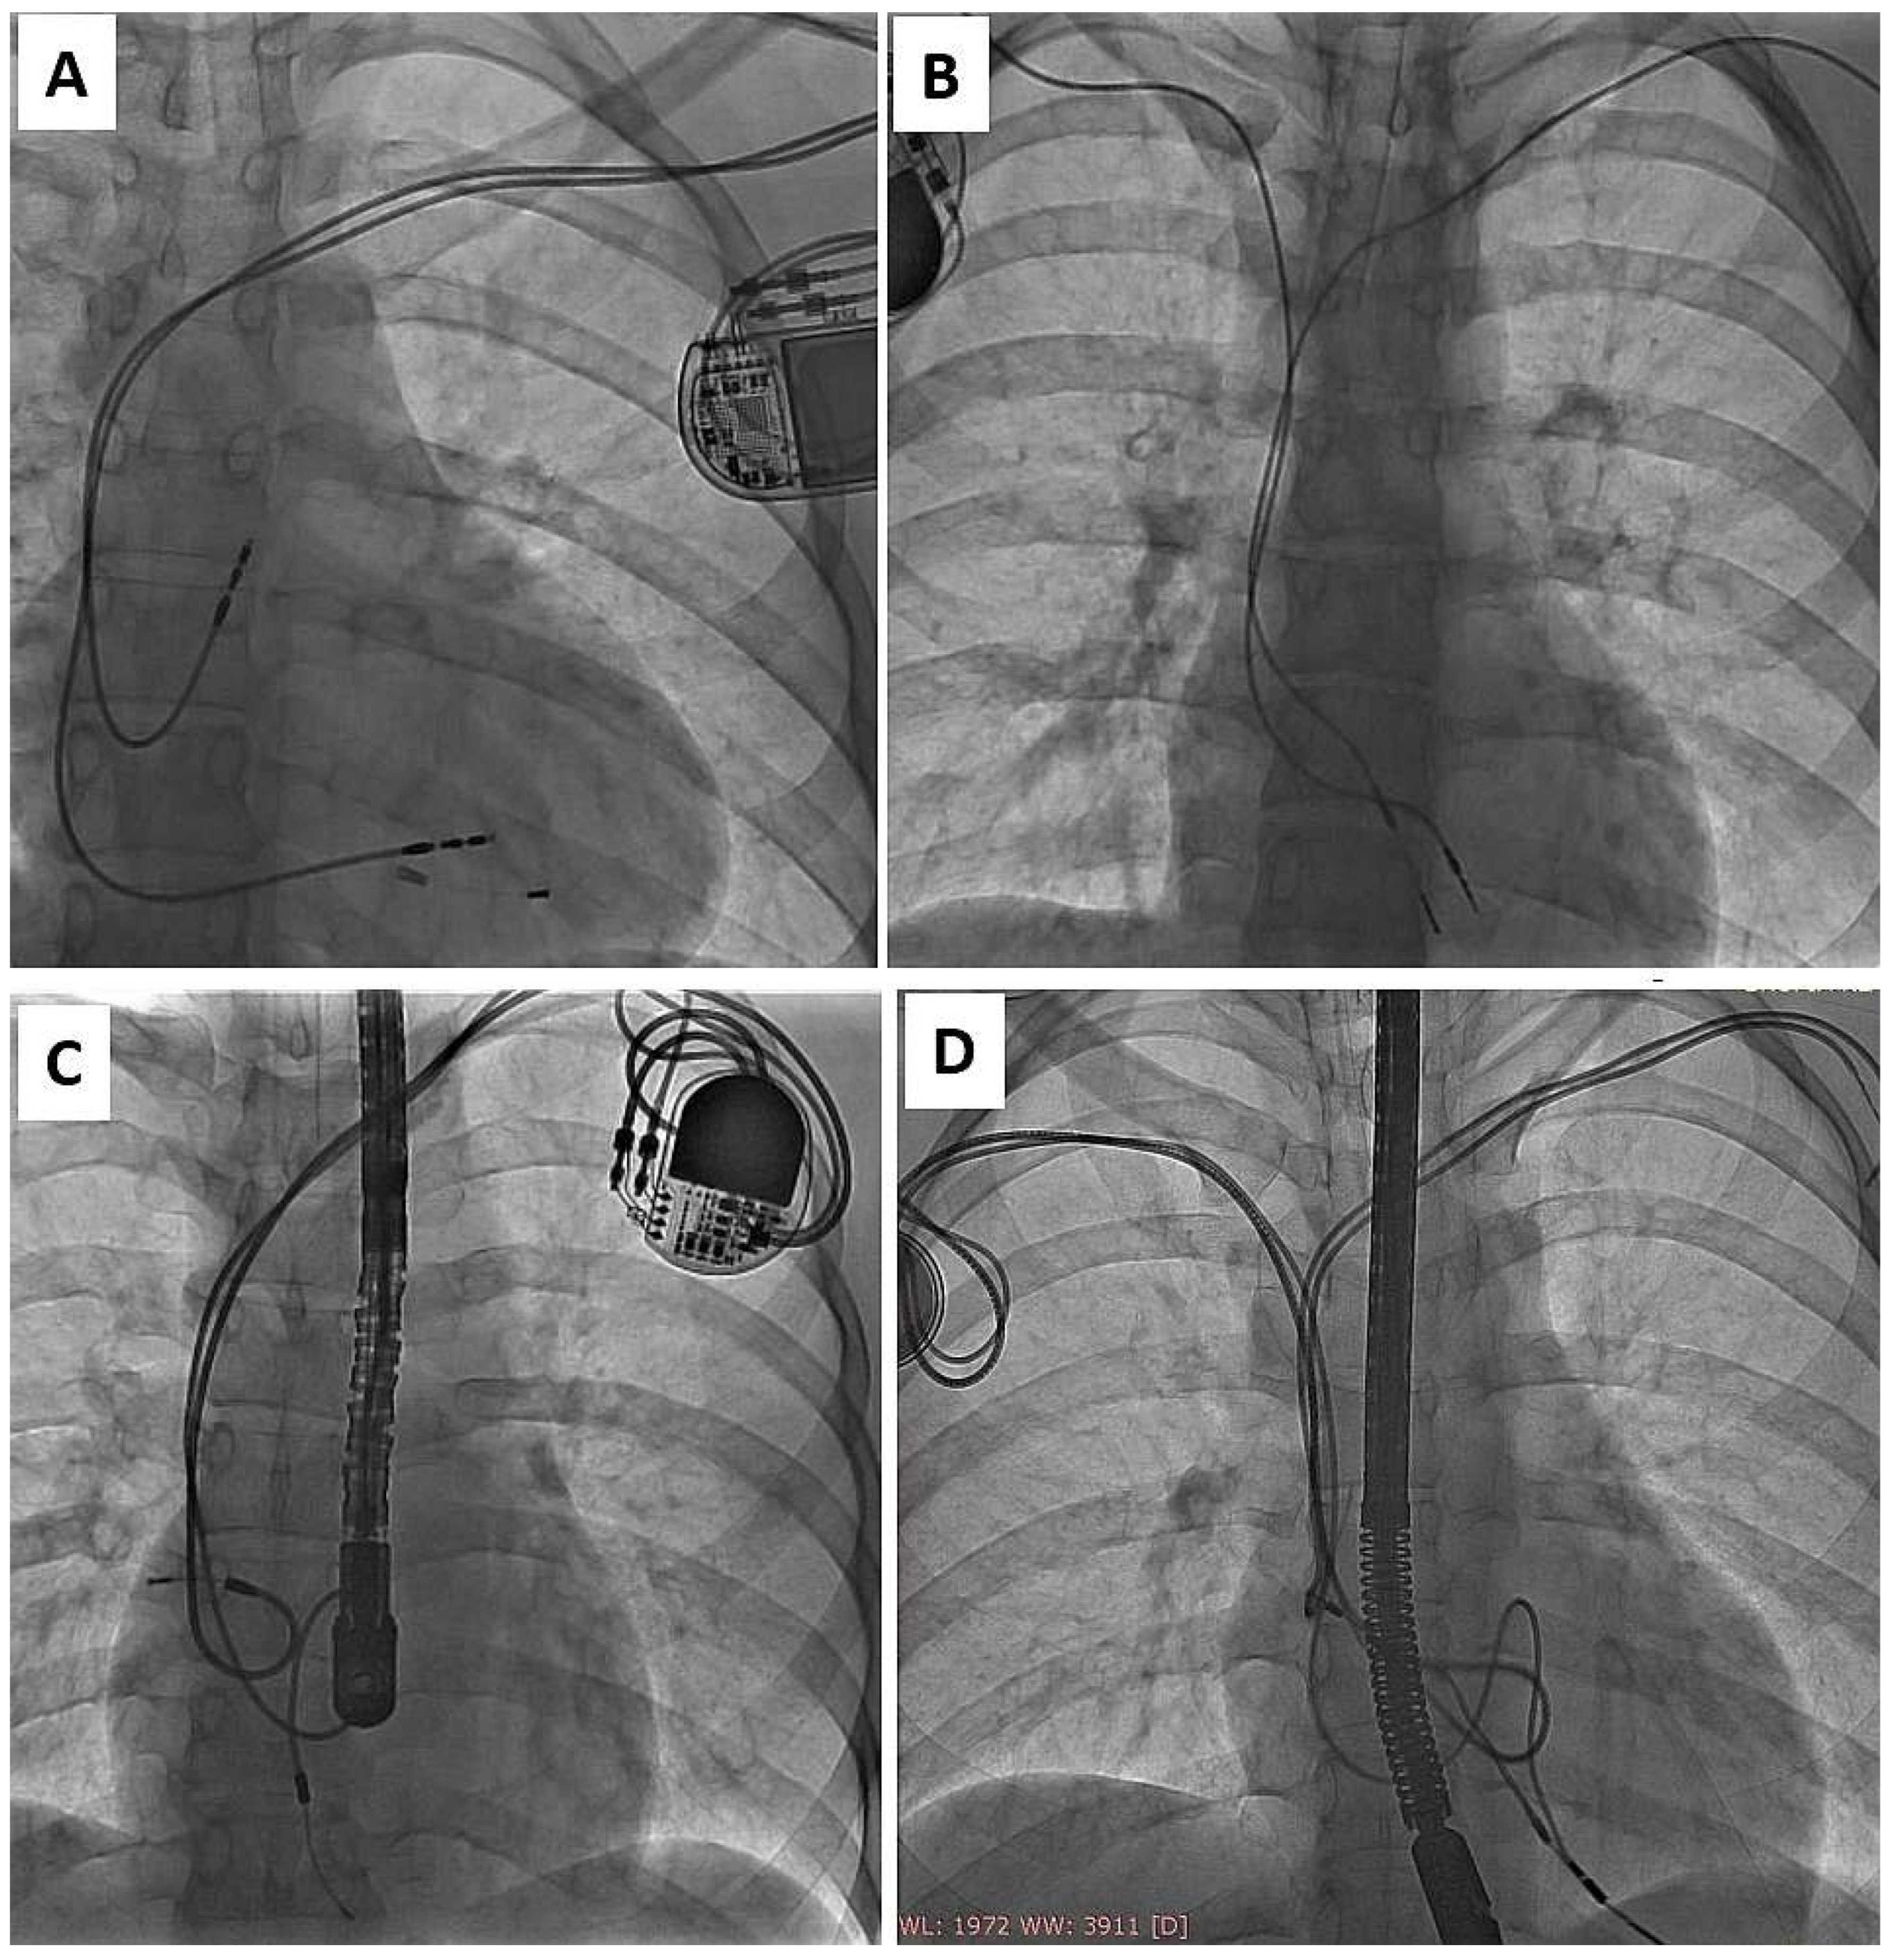

Finally, most young adults become candidates for lead extraction in adult centers or, receive new leads, and the next occasion for removal of all old leads is lead dysfunction or infection [33]. The adverse effects of lead abandonment in adults have been shown in several studies involving large patient populations [19,25,29,30,35]. Nobody has described abandoned lead-related problems in CIP patients, but our experience shows that a strategy of lead abandonment in children, juveniles, and young adults may create much more serious problems 10 to 20 years later (Figure 3).

Figure 3.

Common preoperative radiological imaging of adult patients with leads implanted in childhood, reflecting their history of electrotherapy in the form of remnants of lead fragments after TLE (A), abandoned leads (B,D) or unnecessary lead loops in the heart, which did not prevent constant pulling on the RV apex and partial destruction of BP passive lead (unnaturally increased tip-ring distance) (C). (A) Remnants of lead fragments after previous TLE. (B) Presence abandoned lead opposite chest side. (C) Two abnormal lead in right atrium, partial destruction of BP passive lead (unnaturally increased tip-ring distance). (D) Two abandoned leads left side of the chest. Redundant lead slack (but planned) generates risk of strong adherence to heart structures and to both functional leads and finally-very difficult extraction.